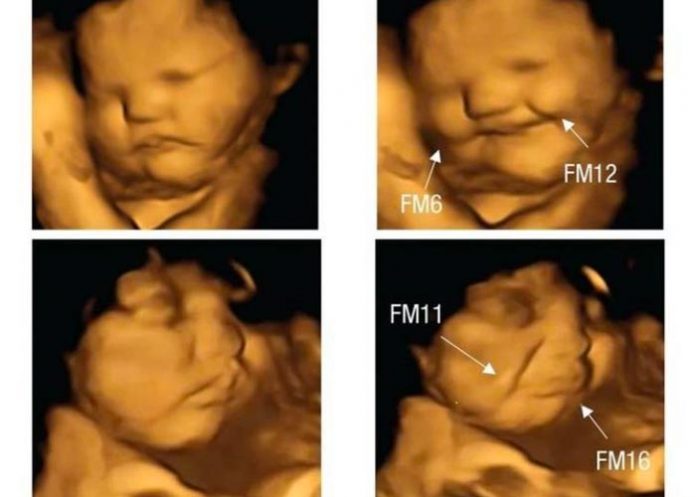

Estas imágenes han permitido observar la forma en la que los futuros bebés reaccionan cuando su madre come zanahoria o col rizada. Ante la zanahoria, los fetos mostraron una «cara riendo«; mientras que los que cuya madre había comido col, tenían una «cara llorosa»; afirmaron los científicos.

Fotos de fetos que reacciona según lo que coma mamá